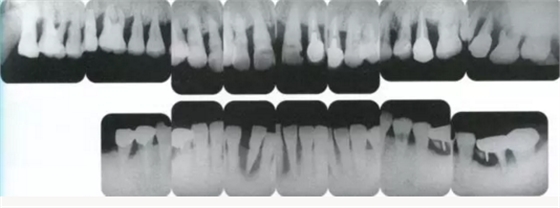

3333.png

▲圖19-12

同時期的X光片。

33333.png

▲圖19-13

佩戴最終修復(fù)體時的正面照片。

333333.png

▲圖19-14

佩戴最終修復(fù)體時的X光片。骨邊緣水平平坦,探診值維持在1~2mm。